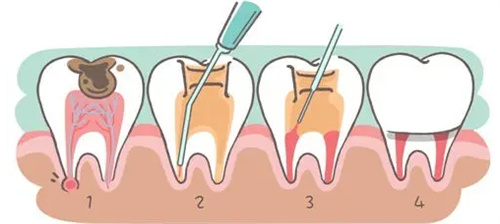

前牙根管治疗:389元至850元/颗。

后牙根管治疗:269元至938元/颗。

显微根管治疗:1000元起/颗。